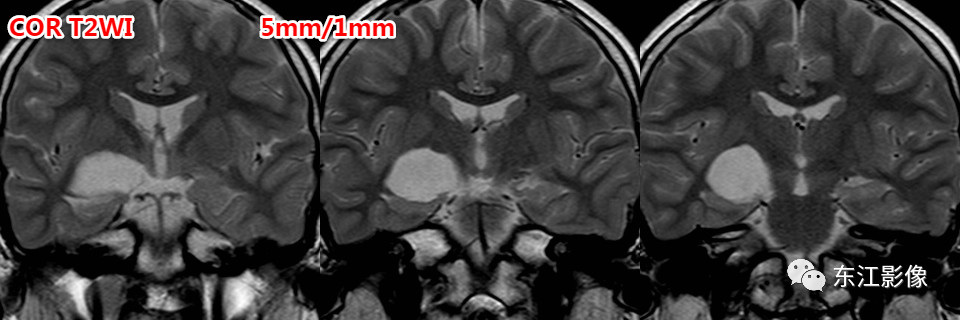

薄层扫描有助于这类小腔隙样灶的鉴别。

腔隙灶多为软化灶,FLAIR边缘多呈高信号,边缘不光整,无泪滴状或纺锤样外观。